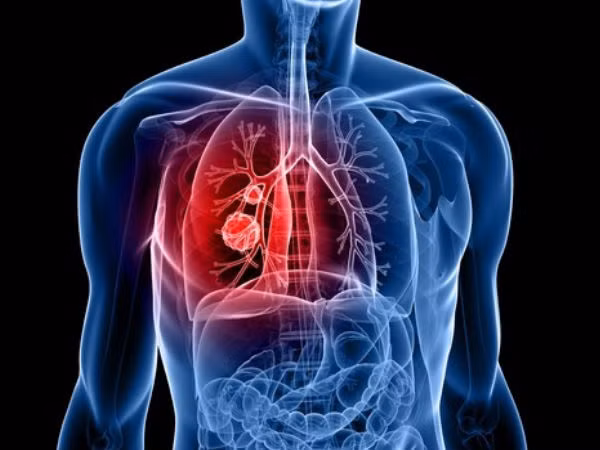

| Tranh thủ kỳ nghỉ đông, Lý Thiến Sơn đến bệnh viện địa phương khám. Kết quả ban đầu không mấy khả quan nên bác sĩ chỉ định thực hiện thêm nhiều xét nghiệm khác. Kết quả cho thấy, Lý Thiến Sơn mắc ung thư phổi. (Ảnh minh họa) |

| Tế bào ung thư đã di căn tới gan khiến bệnh nhân đau bụng dữ dội. May mắn thay, khối u của Lý Thiếu Sơn được kiểm soát, những cơn đau bụng cũng không còn. Ảnh: Boldsky. |